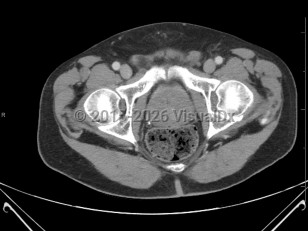

Benign prostatic hyperplasia

Management includes modifications in routine (limiting fluids at bedtime, caffeine intake, and diuretics) and medications. BPH can cause acute urinary retention, which requires catheterization. Patients with poor results may seek surgical treatment such as prostatic urethral lift, transurethral resection of the prostate, transurethral incision of the prostate, or prostate laser surgery.